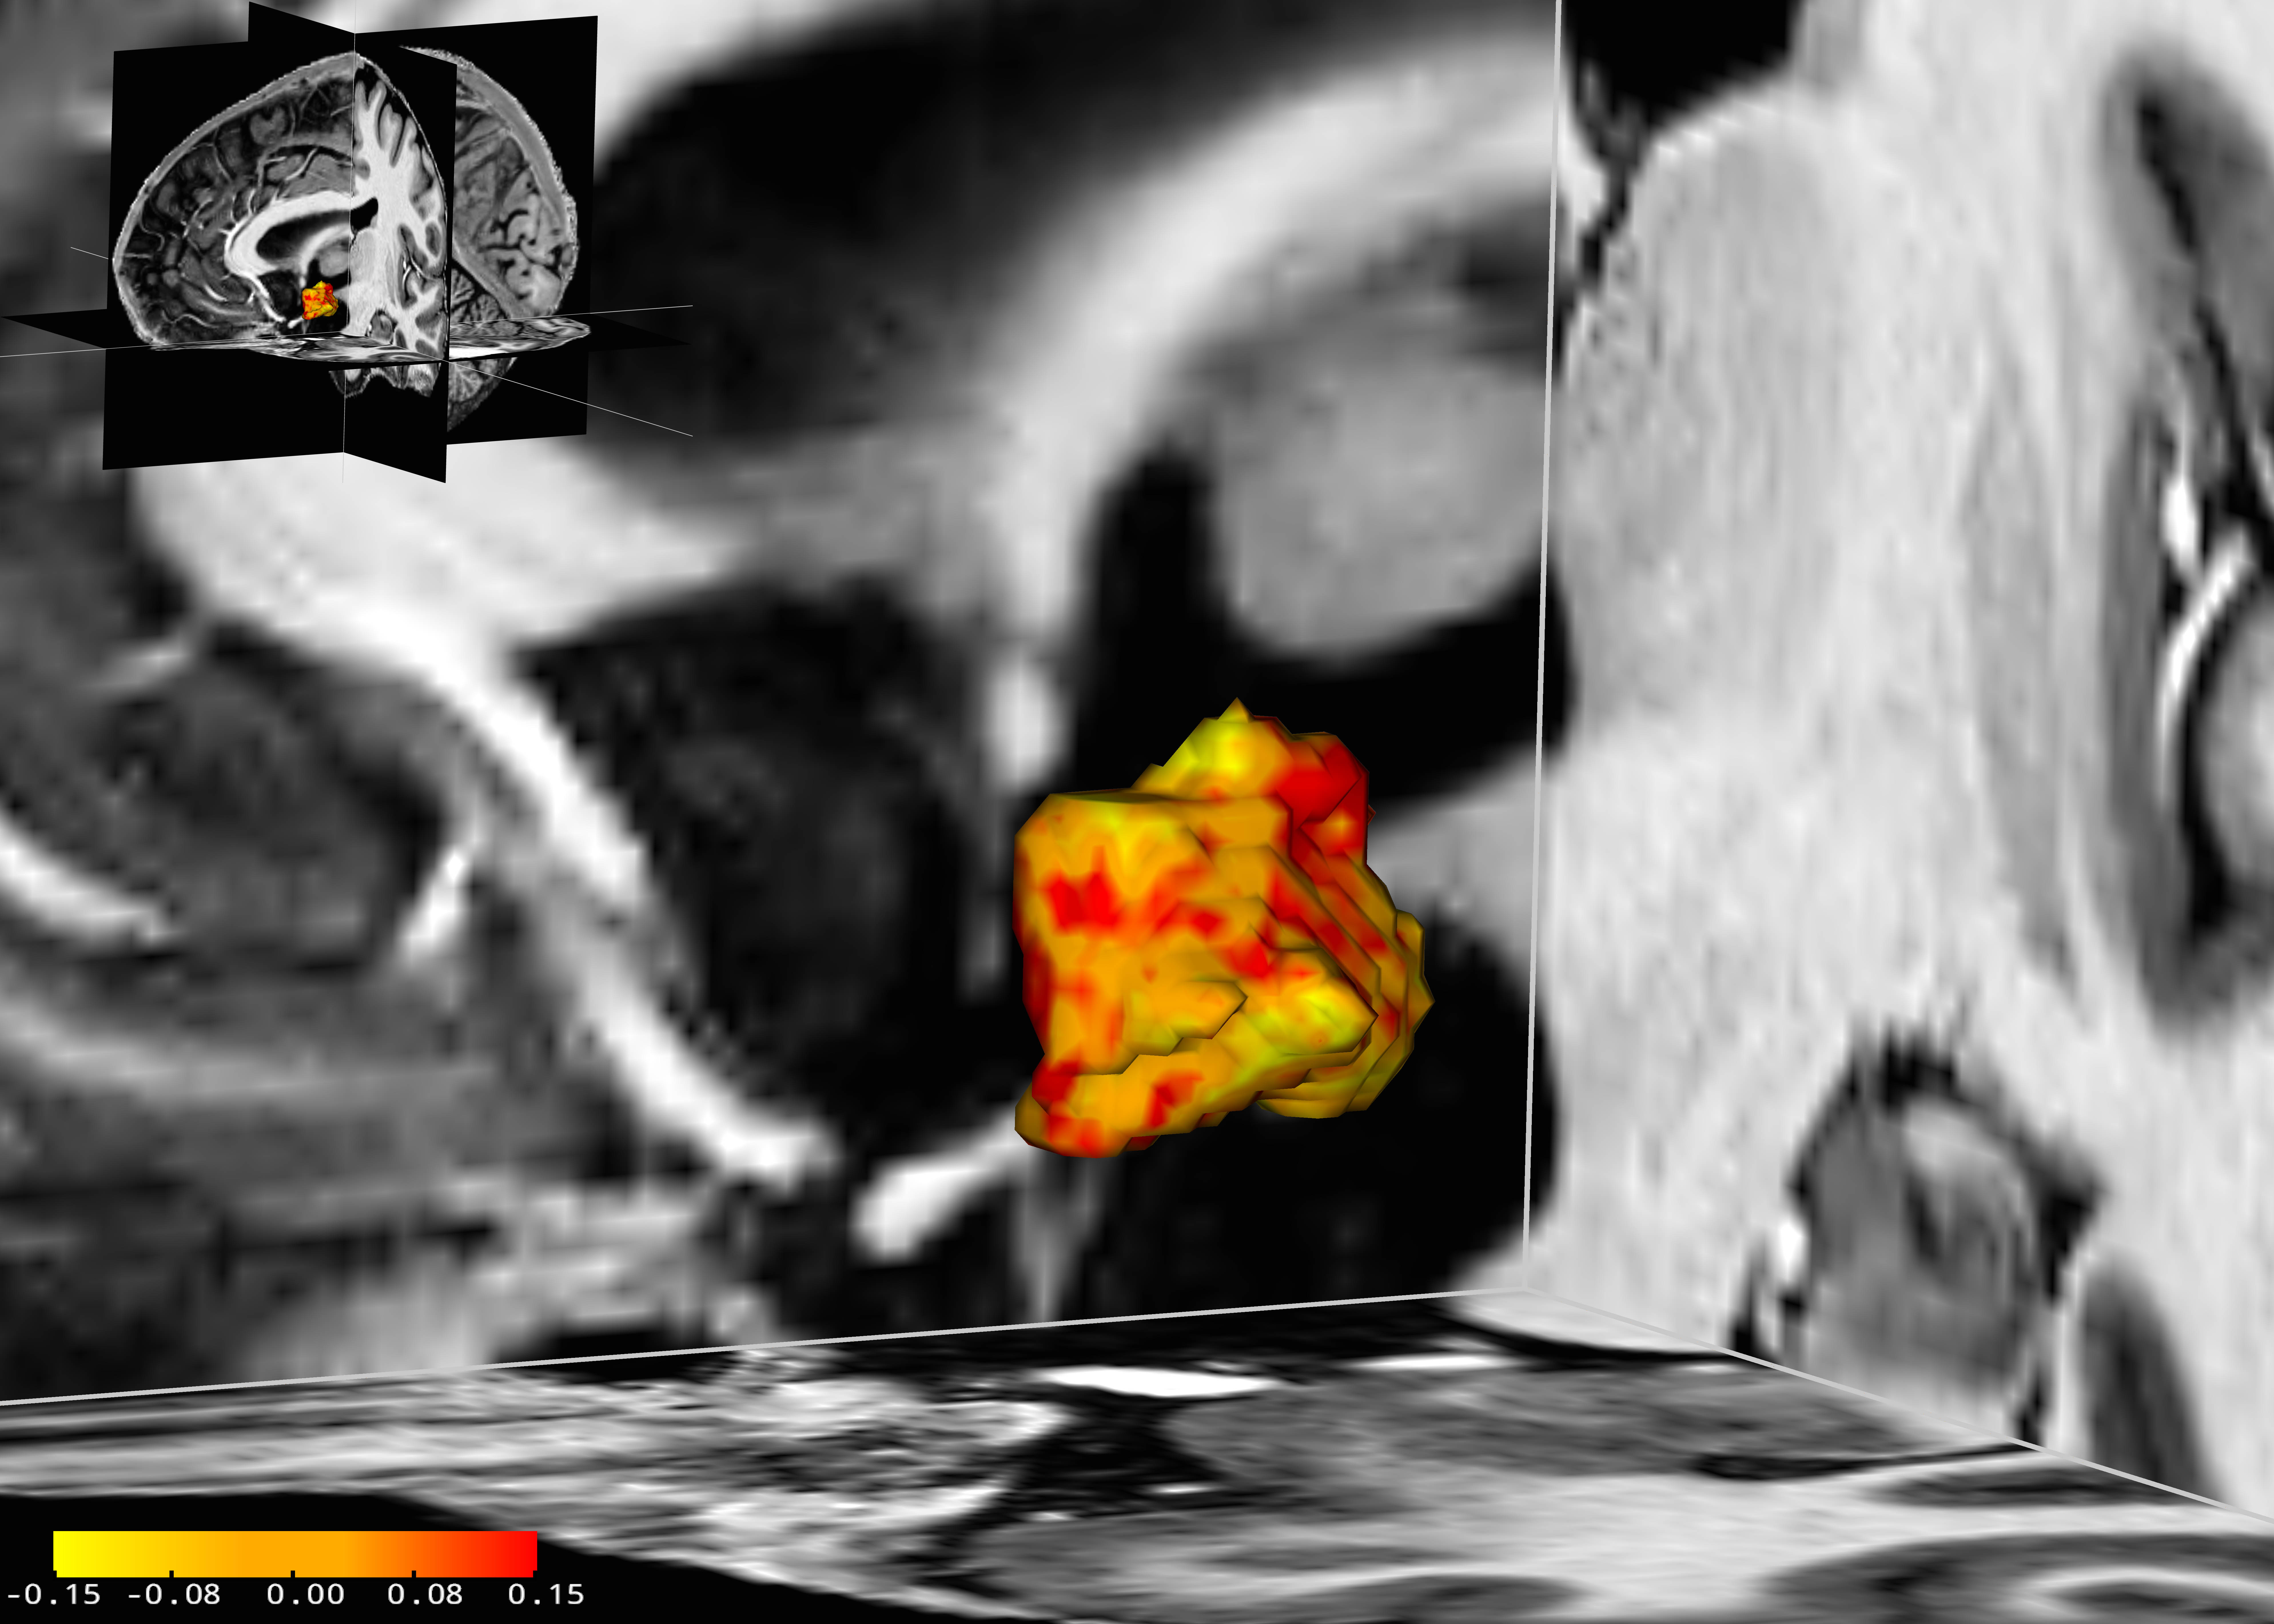

In a recent study with 84 participants, scientists at the Max Planck Institute for Human Cognitive and Brain Sciences (MPI CBS) in Leipzig and the Department of Psychiatry and Psychotherapy of the University Clinic in Leipzig have revealed that in people with an affective disorder, the left hypothalamus was on average five per cent larger than that of their healthy counterparts. “We observed that this brain region is enlarged in people with depression as well as in those with bipolar disorder, two types of affective disorders”, says Stephanie Schindler, a PhD student at both research institutes involved in the study and first author of the underlying publication just published in the scientific journal Acta Psychiatrica Scandinavica. Furthermore, in one of the groups of participants with depression it was also revealed that the more severe the depression, the larger the hypothalamus was. Medication did not have any effect on the size of the hypothalamus.

These relations were found out using a high-resolution 7-Tesla MRI scanner. The severity of disorders was measured using standardised questionnaires and interviews.

Although studies have shown this brain structure to be more active in people with depression or bipolar disorder, it is not yet known what role a larger hypothalamus plays. “Higher activity could lead to structural changes and thus to a larger volume of the hypothalamus normally the size of a one cent coin”, says Stefan Geyer, one of the study’s principal investigators and head of the research group Anatomical Analysis of the Organization of the Human and Non-Human Primate Brain at MPI CBS.